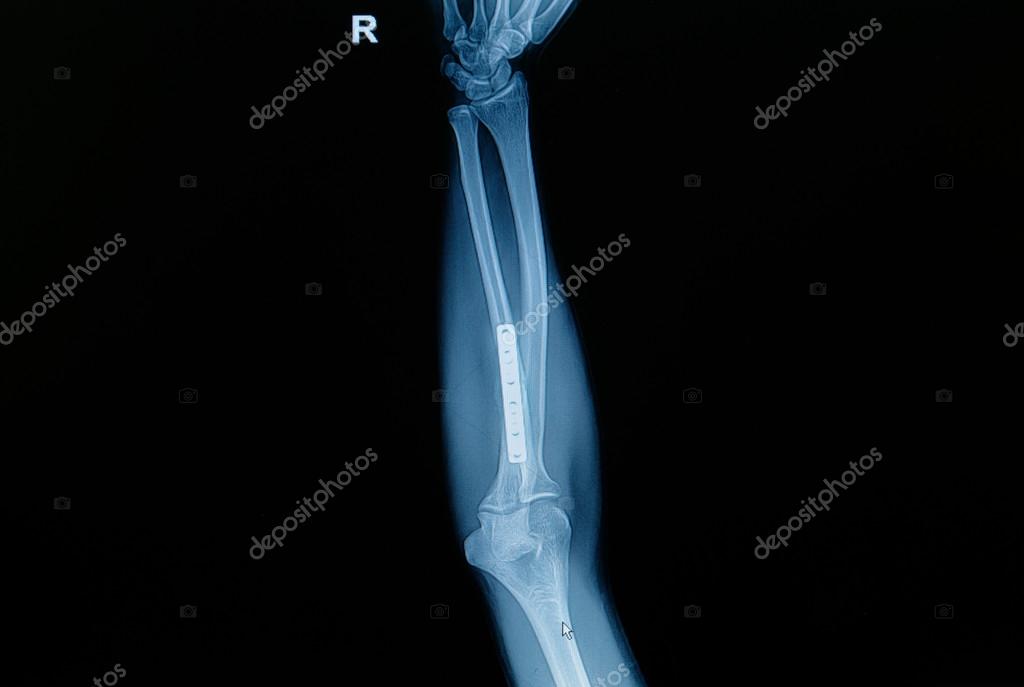

Перелом локтевой и лучевой кости . Чаще встречается нарушение целостности обеих костей предплечья в диафизарной части, это возникает при сильном ударе . Снимок делается в двух проекциях . Это дает возможность оценить степень и направление смещения фрагментов .

Локтевой отросток интактен . Фиксация перелома плечевой кости потребует остеотомии локтевого отростка для доступа к плечевой кости . Здесь можно видеть боковую проекцию у этого же пациента после оперативной репозиции двухмыщелкового перелом плечевой кости .